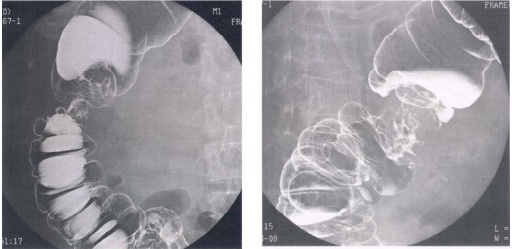

74 80 歲林先生,近來感覺疲倦、頭暈。家人說他瘦了,皮膚蒼白。血液檢查肝功能正常,進而為他做 鋇劑灌腸 X 光攝影檢查,影像如圖示。林先生最可能患了什麼病?

(A)潰瘍性大腸炎(ulcerative colitis) (B)結腸套疊(intussusception) (C)克隆氏疾症(Crohn’s disease) (D)結腸癌(colon cancer)